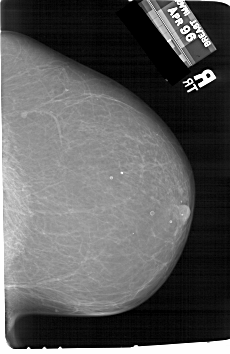

A_1204_1.RIGHT_MLO

RIGHT_MLO LINES 6526 PIXELS_PER_LINE 4456 BITS_PER_PIXEL 12 RESOLUTION 43.5 NON_OVERLAY